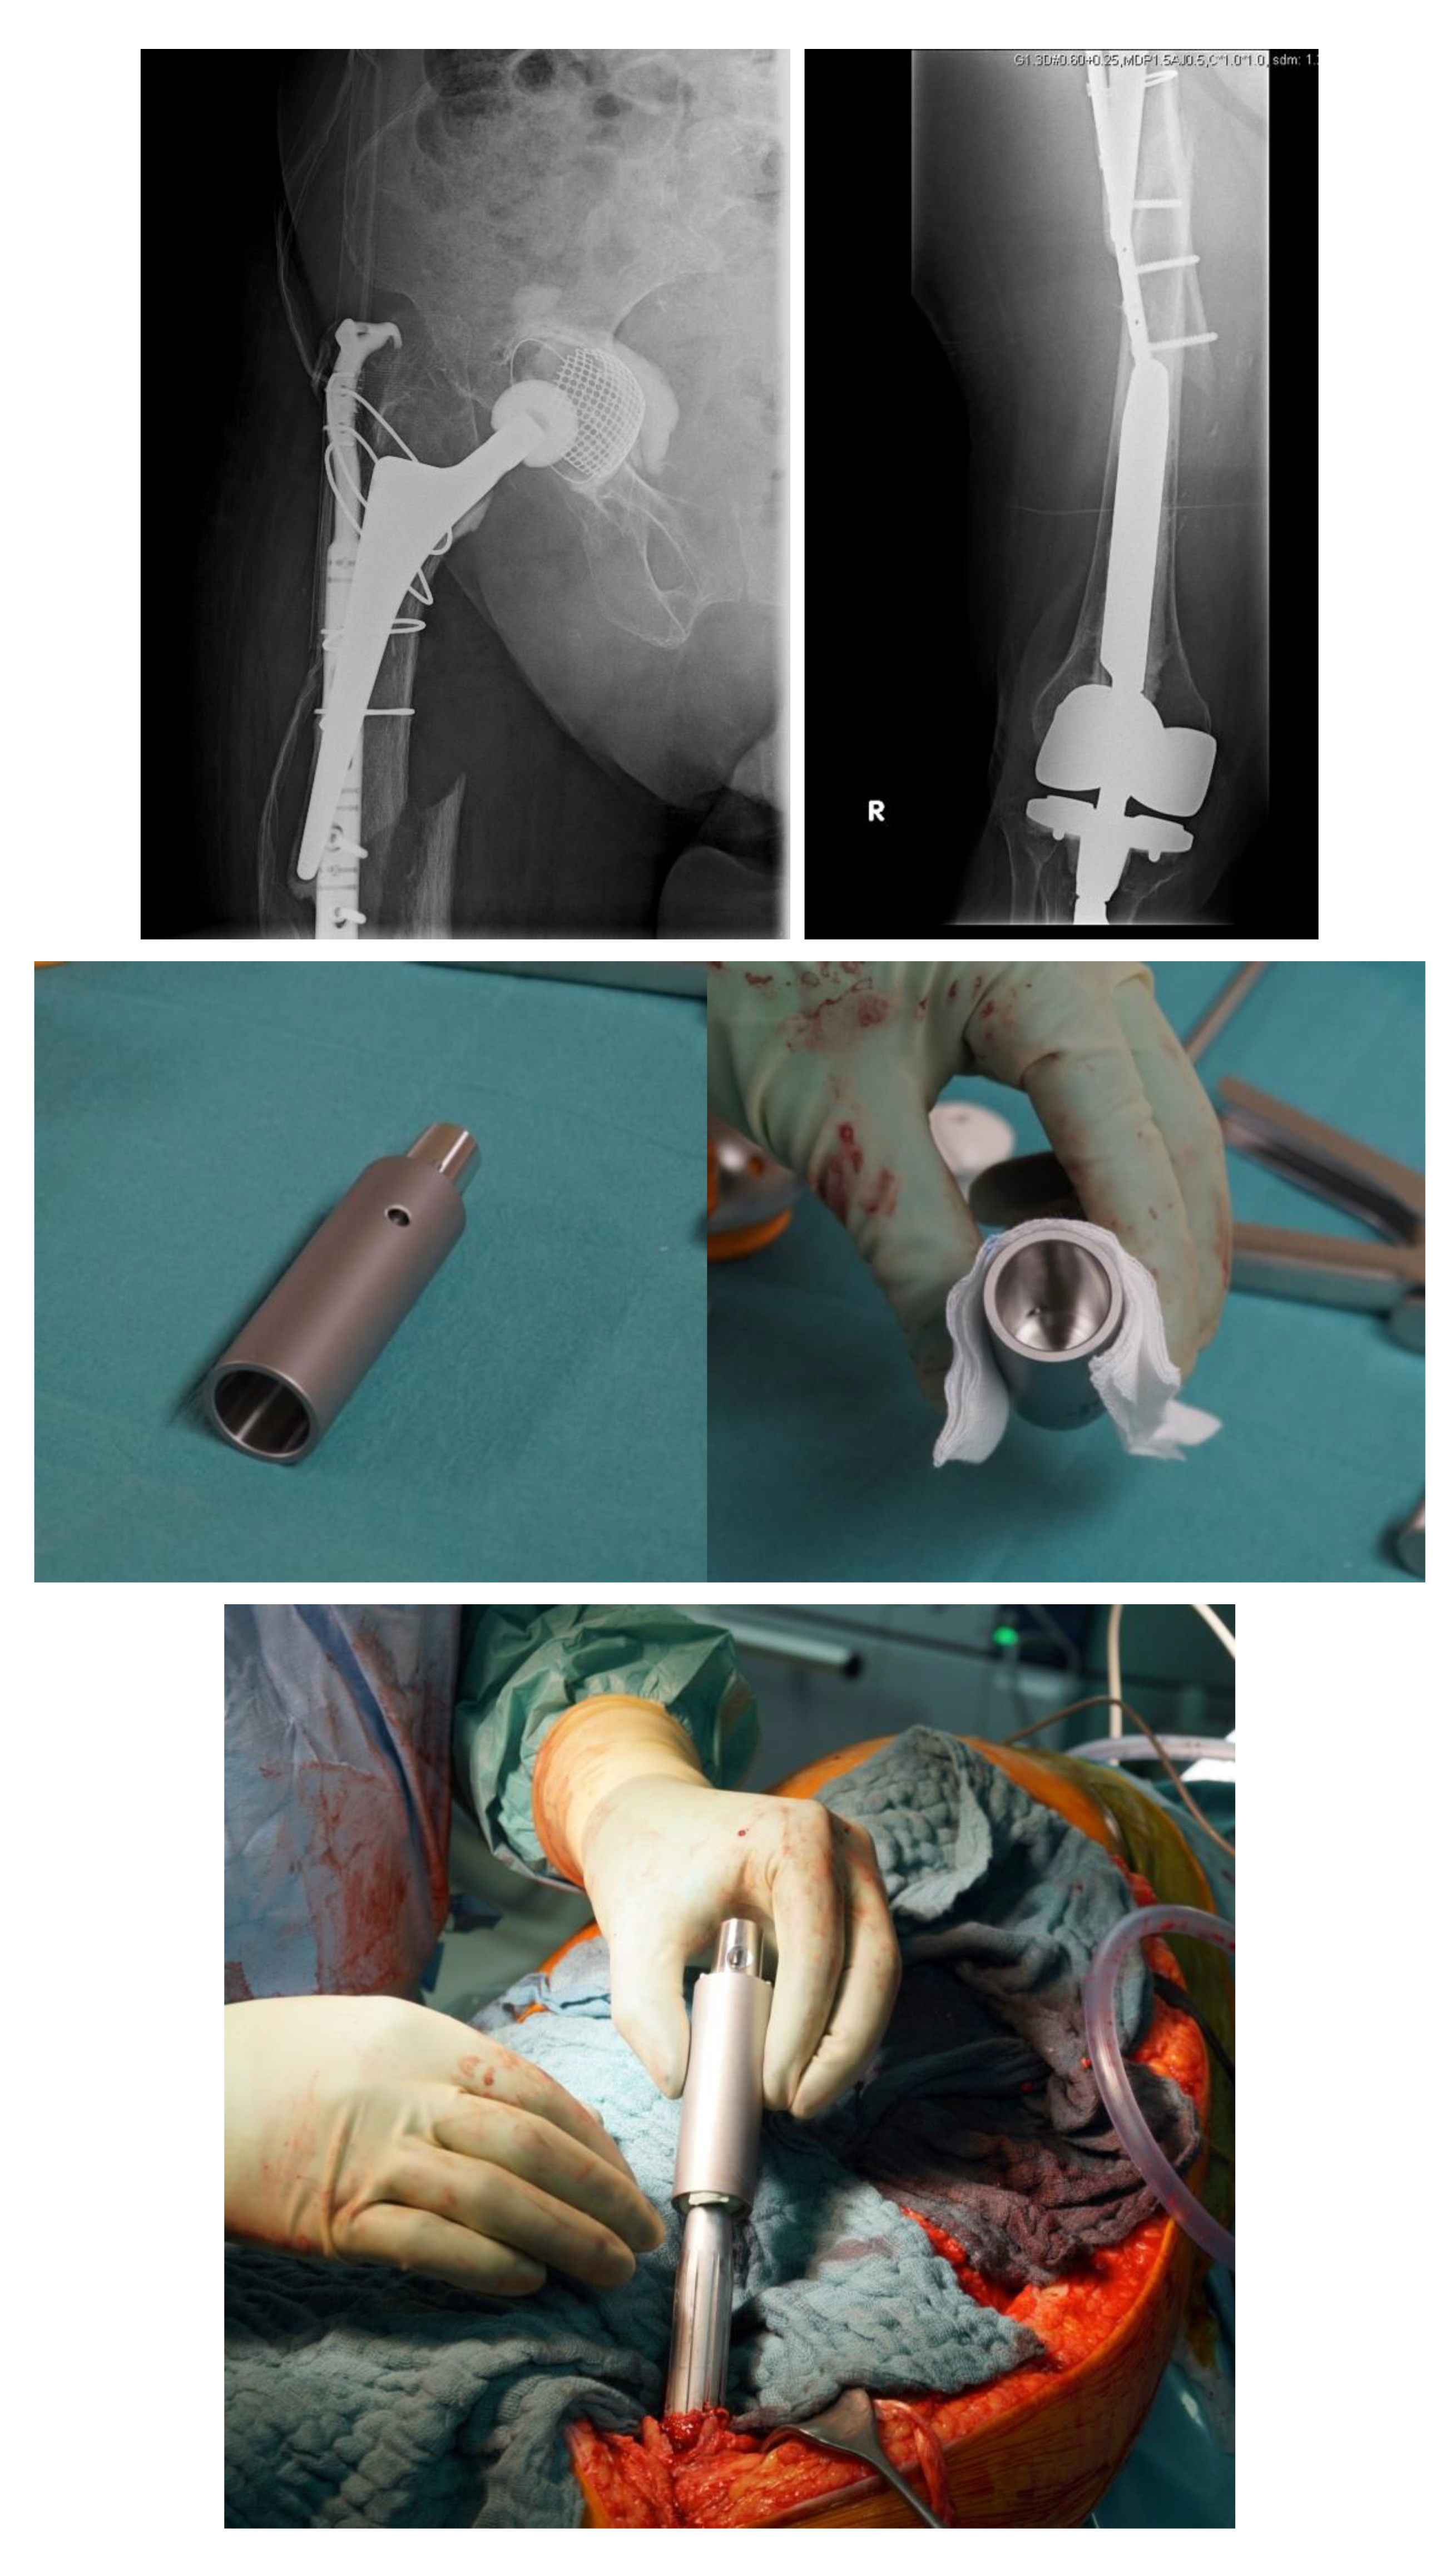

Hence, a special concept improving the bicortical screw fixation around intramedullary devices called the LOQTEQ® VA Periprosthetic Plate or ‘periprosthetic hinge plate’ was established by the company, aap Implantate AG. Multiple insertable hinges create the possibility to place the screws bicortically and alongside the enclosed stem. The square of the two polyaxial locking screws of the hinge constitutes 15 degrees to each direction. Since a central screw can be attached separately, further angle stabilization of the hinges can be achieved. The hinge is not attached to a plate hole, which could be staffed additionally with monocortical screws or cable cerclages in the diaphysis (Figure 3).

Figure 3. (a) LOQTEQ VA Periprosthetic Plate (with kind permission of aap Implantate AG, Berlin, Germany). (b) Insertable hinge with each of the two variable angle screw options (with kind permission of aap Implantate AG, Berlin, Germany). (c) Periprosthetic fracture around a cemented stable total hip revision arthroplasty. (d) LOQTEQ VA Periprosthetic Plate with mounted aiming device. (e) LOQTEQ VA Periprosthetic Plate with four inserted hinges. (f) Variable angle screw placement around the hip revision stem. (g) Postoperative X-rays. Four hinges with each of the two variable angle screw options were used to fix the plate around the hip stem.